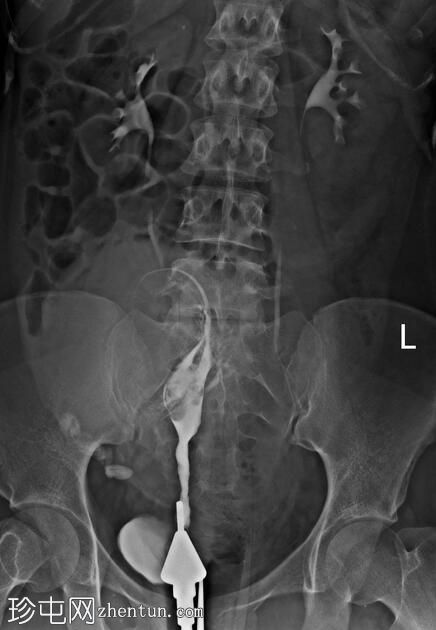

注射更多造影剂后,造影剂渗入子宫肌层静脉和右侧性腺静脉,随后进入肾静脉。

手术开始三分钟后,造影剂进入肾脏,充盈肾盂肾盏系统,然后流入输尿管和膀胱,形成类似于静脉肾盂造影(IVP)的影像

子宫输卵管造影术中出现类似静脉肾盂造影的影像提示可能存在输卵管阻塞,这是由于造影剂流入输卵管并随后流入性腺静脉受阻所致。